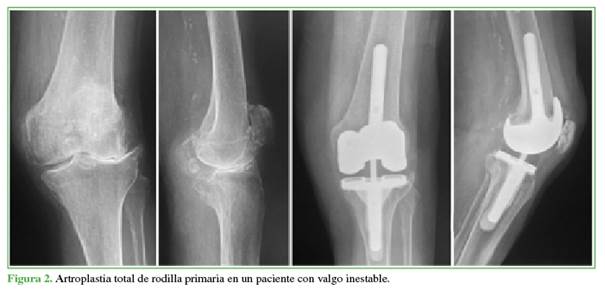

No se hallaron diferencias estadísticamente significativas en la cirugía (primaria o revisión) y el tiempo de seguimiento entre los subgrupos (Figuras 1 y 2).